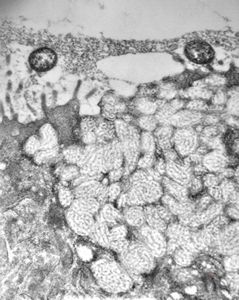

normal mucosa - stomach - parietal cell